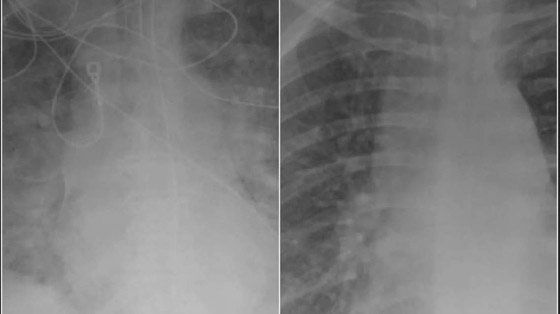

وأوضح الدكتور دوراني أن المرضى الذين تم تطعيمهم والذين أصيبوا بفيروس كورونا لديهم المزيد من الهواء المتدفق إلى رئتيهم، مع تلوين الجزء الأكبر من الرئتين باللون الأسود في الفحص، وهذا يعني أن هناك ضررًا ضئيلًا جدًا أو لا يوجد ضرر على الرئتين. وتظهر صورة الفحص من شخص غير محصن أن الرئتين محتقنتان للغاية، مما يحد من تدفق الأكسجين في جميع أنحاء الجسم.

وقال الدكتور دوراني "إذا كان لديك مريض تم تطعيمه يأتي إلى غرفة الطوارئ مصابًا بعدوى غير مسبوقة، ربما يكون لديه ضيق في التنفس، ونقوم بإجراء فحص بالأشعة المقطعية، فستجد أن حالته ليست بنفس سوء حالة المرضى غير المطعمين. وحتى حالات العدوى الخارقة التي ينتهي بها المطاف بالإصابة بالالتهاب الرئوي، فإن فحوصات التصوير المقطعي المحوسب لم تكن سيئة مثل تلك الخاصة بالمرضى غير المطعمين". وتُظهر البيانات من المراكز الأمريكية لمكافحة الأمراض والوقاية منها أن خطر الوفاة من كورونا أعلى بـ 11 مرة بالنسبة للبالغين غير المطعمين من أولئك الذين تم تلقيحهم.